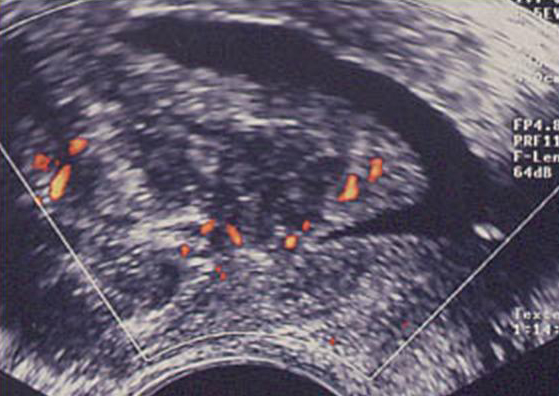

Hystérosonographie. Image intra-cavitaire vascularisée au doppler couleur

Adénocarcinome de l’endomètre